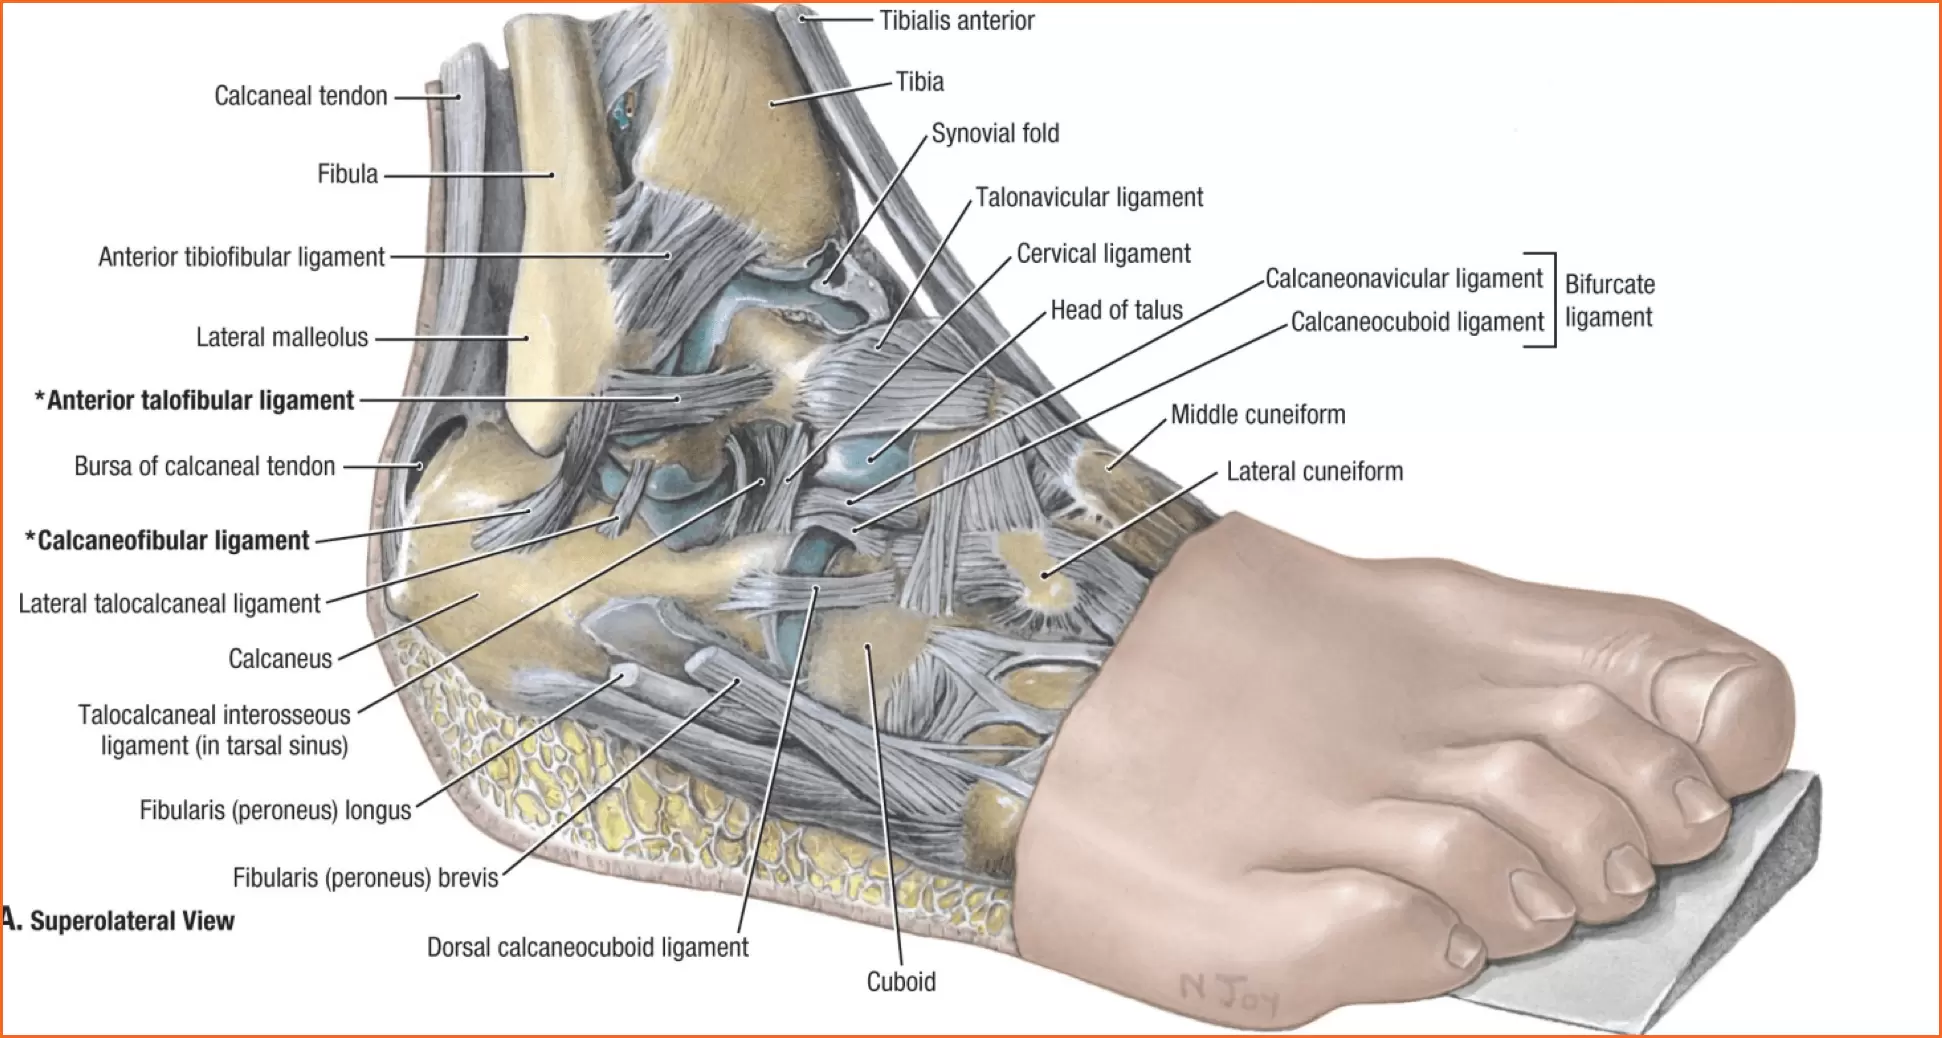

Анатомические фото голеностопного сустава и его суставных поверхностей